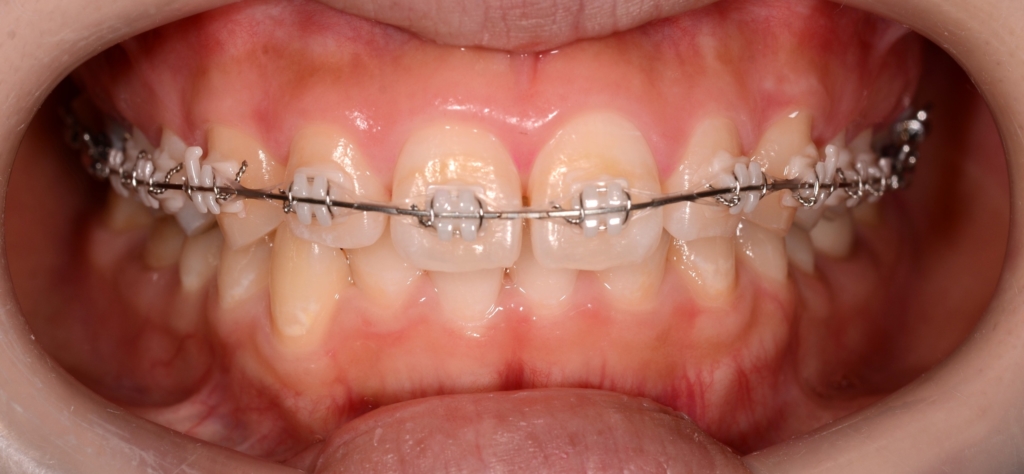

マルチブラケットシステム(スタンダードtype)で矯正を開始

【治療開始】

患者さんの治療の優先順位として、ガミースマイルの改善が第一希望でした。

そこで、先ずは上顎のみ装置を付けて、矯正治療を開始しました。

【ガミースマイルの改善】

ステップが進み歯列が揃ったところで、ガミースマイル改善のために、上顎にアンカースクリューを植立することにしました。

部位は、上顎の口蓋の真ん中、臼歯部(左右側とも)と前歯部の頬側、になります。

アンカースクリューを用いて矯正力を加えることで、上顎歯列全体を圧下させて、ガミースマイルの改善を図ります。

順調に矯正治療は進み、ガミースマイルはほぼ改善されました。